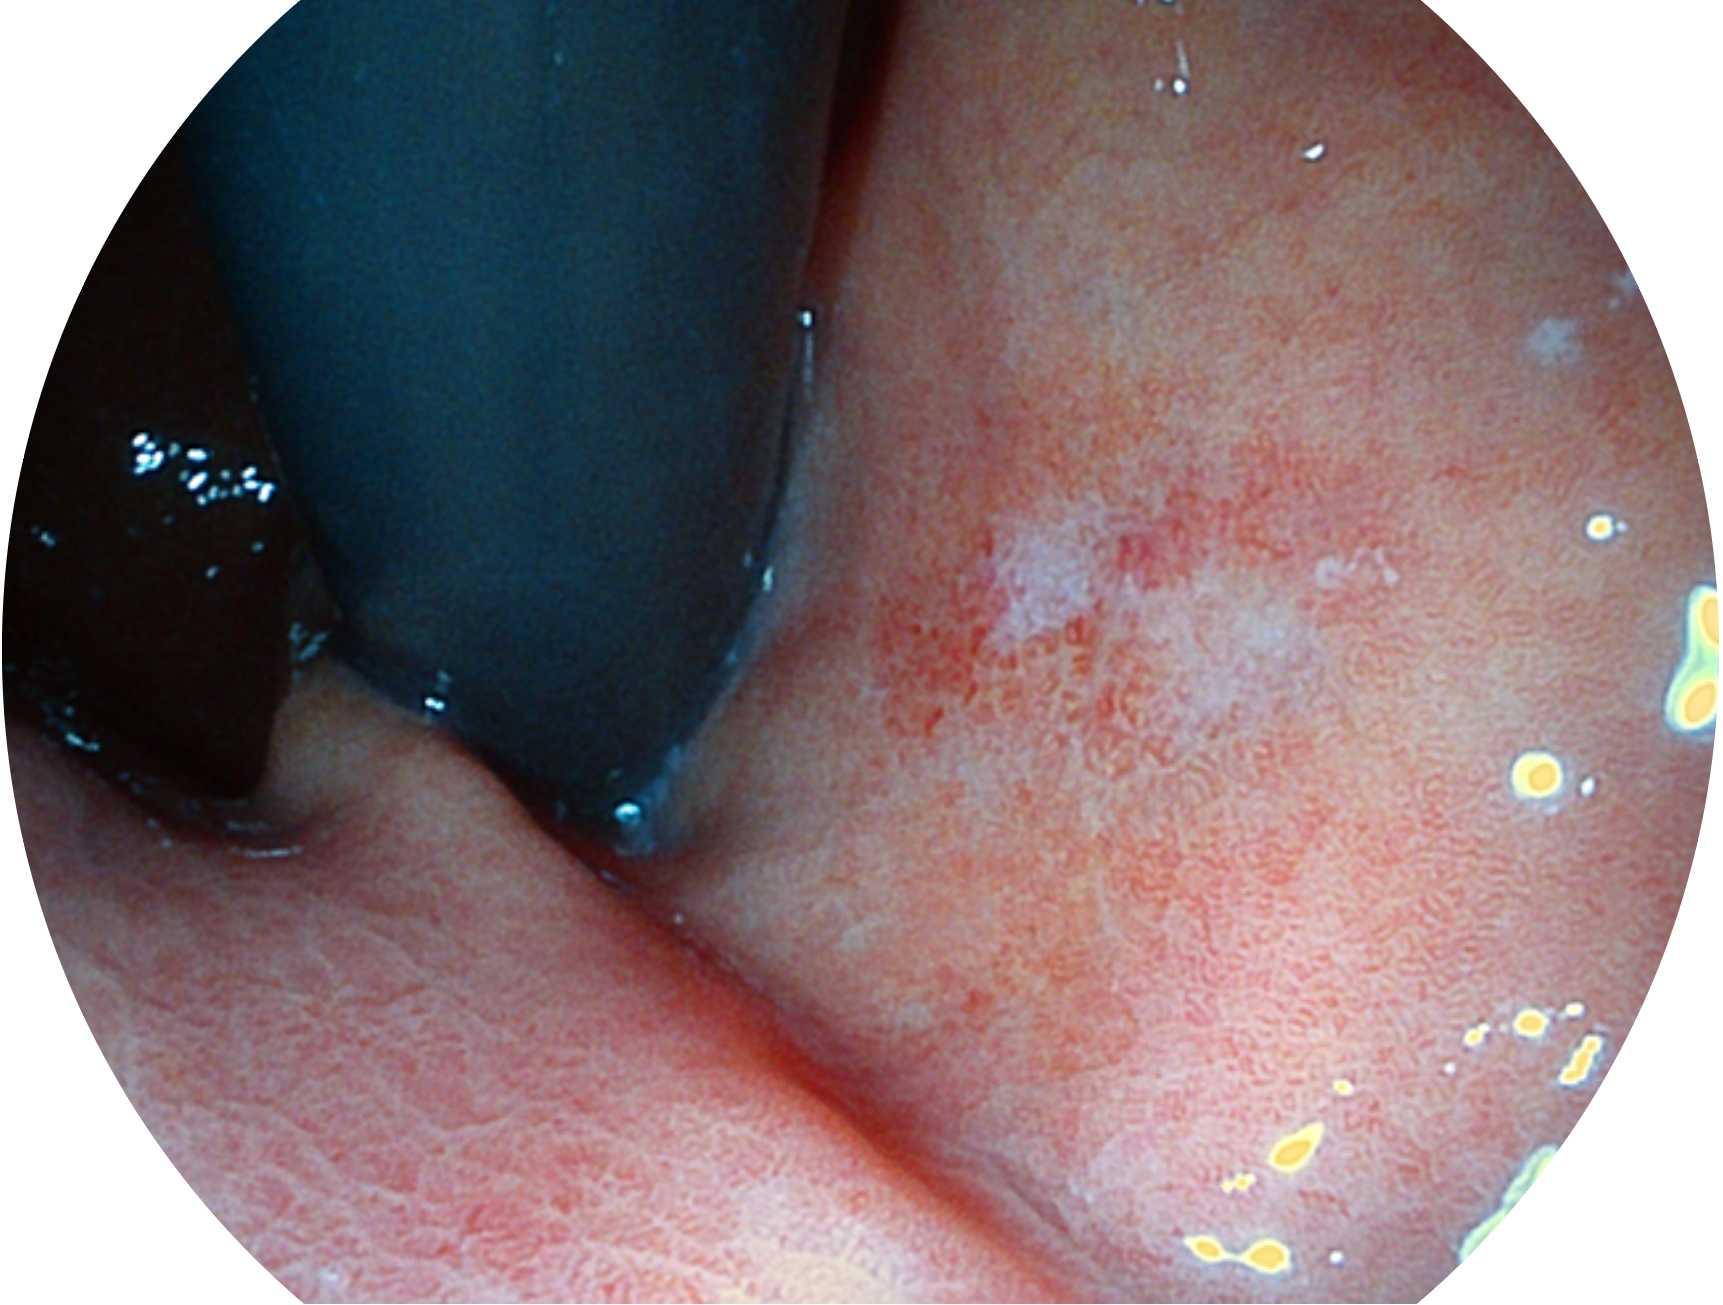

新葡的京集团8814检测站新开发的内镜染色技术,主要是基于多波长LED 光源的开发,VLS-55Q 四波长LED 光源是由四个不同颜色的LED光按照相应照明模式所规定的特定发光比例进行合束后形成,合束后形成的照明光的光谱由红光、绿光、蓝光及蓝紫光这四个不同的波段范围构成。具有更高光谱自由度,通过光谱比例的控制,实现了聚谱成像技术,英文全称为“Spectral Focused Imaging, SFI”,缩写为“SFI”和光电复合染色成像技术,英文全称为“Versatile Intelligent Staining Technology, VIST”,缩写为“VIST”。